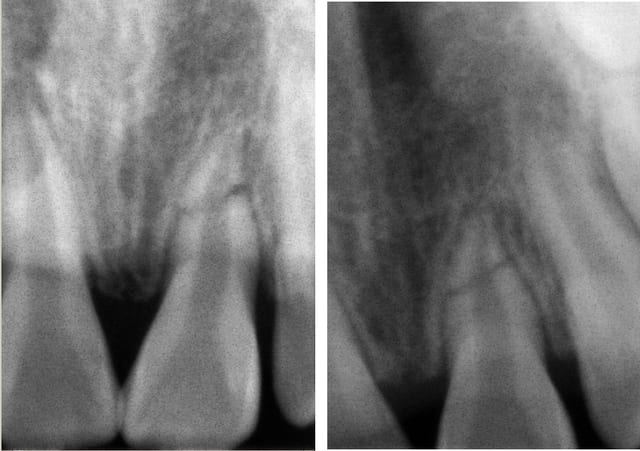

Le hic c'est un belle fracture radiculaire entre le tiers médian et le tiers apical de la racine.

Si tu n'as pas de fracture coronaire associée et qu'il n'y a pas d'écart entre les 2 fragments, le pronostic n'est pas mauvais pour une fracture du tiers apical. Surtout qu'à 8 ans, l'apex est immature : donc la zone de vascularisation large.

Il n'y a pas eu déplacement des fragments, il se font toujours face (enfin en 2D en tout cas..), l'apex est quasi terminé.

Désolée pour le retard, voici les radios de la 21